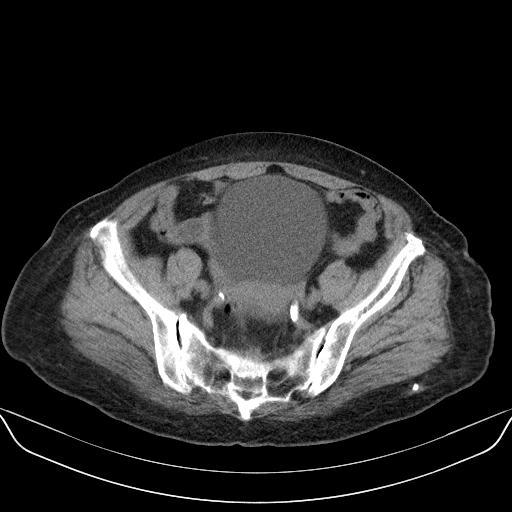

以下是引用yuhongjun在2010-3-12 6:32:00的发言:[br]回肠末端间质瘤,不除外阑尾粘液囊腺瘤,臀部注射性肉芽肿钙化. [br] [br]